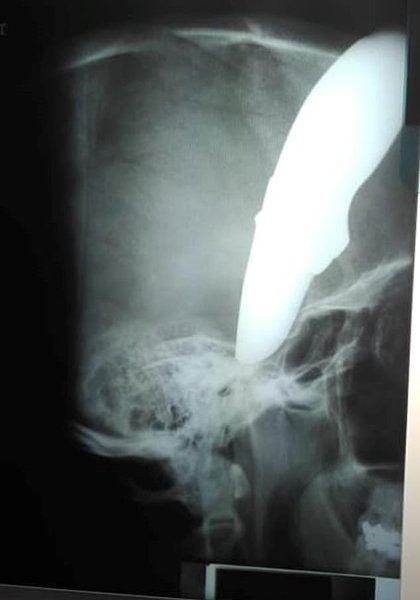

Лезвие длиной 15 сантиметров погнулось о череп и вошло в лицо, не задев мозг.